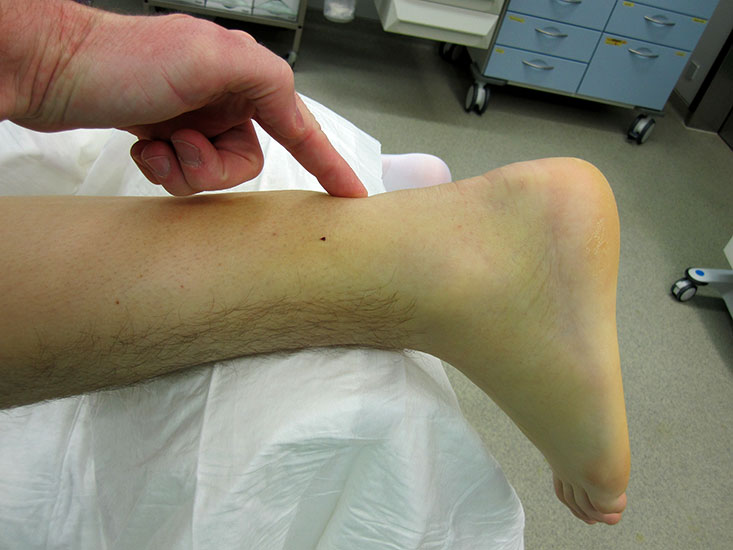

Die klassische traumatische Achillessehnenruptur wird von den Betroffenen meist eindrücklich wahrgenommen. Ein peitschenartiger Knall gefolgt von einem Waden- und/ oder Fersenschmerz, sowie der (partielle) Funktionsverlust führt sie in die weitere ärztliche Behandlung. Hier ist die Anamnese meist das zielführende Diagnostikum. Bei der klinischen Untersuchung präsentiert sich eine tast- und sichtbare Dehiszenz, begleitet von einem lokalen Hämatom. Der Einbeinzehenspitzenstand ist in der Regel nicht mehr möglich.

Abbildung 2

Der Thompson-Test 11 wird durch eine kräftige seitliche Wadenkompression mit der Hand ausgeführt und muss stets im Seitenvergleich erfolgen (Video 1). Die Nomenklatur des Thompson-Tests fällt je nach zitierter Literaturstelle unterschiedlich aus. In unserer Klinik zeigt ein positiver Thompson-Test eine Pathologie, eine Ruptur der Sehne an. Durch den häufig angelegten Muskulus plantaris fällt der Thompson-Test nicht immer vollständig positiv aus. In einigen Fällen lässt sich seine Sehne im Bereich der Rupturstelle palpieren. Ebenfalls können inkomplette Rupturen mit einem falsch negativen Befund imponieren (Abbildung). In unsicheren Situationen kann unterstützend ein leichter Druck mit den Fingern im Vorfußbereich die seitendifferente Kraftausübung beim Test aufzeigen.

Chronische Achillessehnenrupturen unterscheiden sich dagegen häufig in der Anamnese und dem klinischen Bild. Das Unfallereignis liegt in der Regel lange zurück und war – sofern die Patienten sich noch daran erinnern können – eher ein Bagatelltrauma. Bei Patienten mit systemischen Erkrankungen (Diabetes mellitus, Hyperurikämie, Kortisondauertherapie, Antibiotikagabe) ist ein Trauma oftmals nicht der Auslöser für die Ruptur. Hier handelt es sich vielmehr um einen schleichenden Prozess mit rezidivierenden Mikrotraumata und resultierenden Patialrupturen. Subjektiv eingeschränkt sind die Patienten vor allem bei Alltagsbewegungen wie Treppen steigen oder das Laufen auf ansteigenden Rampen. Auffällig häufig stellen sich bei uns Patienten vor, die bei Wanderungen im Gebirge eine Kraftlosigkeit im betroffenen Bein bemerken. Auch beschreiben sie einen diffusen Fersenschmerz. Eine Dehiszenz lässt sich durch die narbige Überbrückung in der Regel nicht palpieren. Eine Ausnahme bilden hier veraltete knöcherne Ausrisse, die eine typische Konturierung der Fersenregion bedingen (Abbildung).

Abbildung 3a

Abbildung 3b